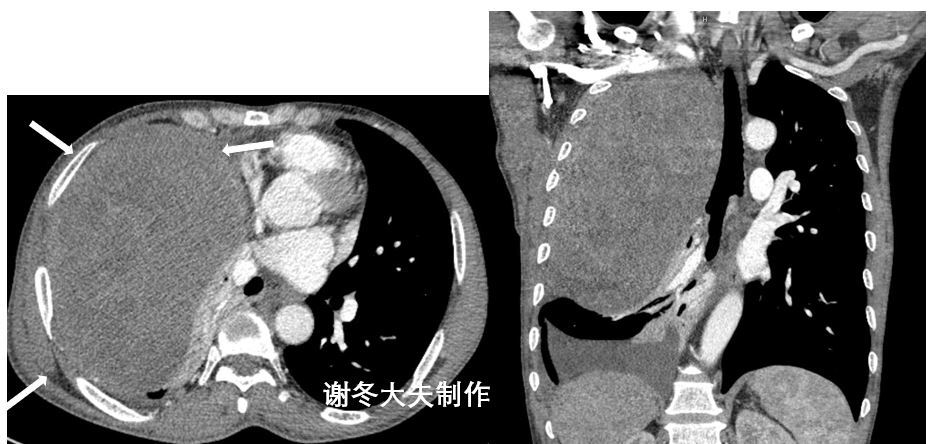

ct横断位见左侧胸腔心脏后方一个巨大的纵隔肿瘤,呈现脂肪密度,中间

患者,女性,73岁,咳嗽,咳痰10余天,在当地医院行平扫诊断为纵膈肿瘤